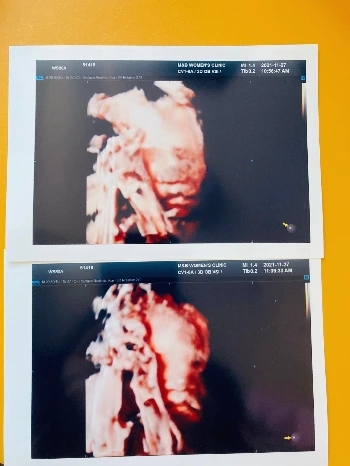

며칠 전, 임신한 와이프와 함께 병원으로 정기 검진을 받으러 갔다. 코로나19 때문에 원래는 와이프 혼자 병원에 들어가서 검사를 받고 나왔는데, 11월부터 보호자 1명도 입장이 가능해져서 임신 7개월 만에 처음으로 산부인과라는 곳을 들어가 보았다. 임산부 당뇨검사를 하고 초음파로 우리 아기의 모습을 실시간으로 처음 보았다. 지난번 방문 때도 입체 초음파를 했지만 아기가 팔로 얼굴을 감싸고 가리고 있어서 제대로 된 얼굴을 못 봤기 때문에 이번엔 기대를 하고 초음파실로 들어갔다.

아기의 심장이 잘 뛰고 있는지 내장이 잘 있는지 먼저 확인을 하고 초음파 기계는 아기의 얼굴로 향했다. 누굴 닮았을까, 기대하고 있었는데, 이번에도 아기는 쉽게 얼굴을 보여주지 않았다. 의사 선생님도 당황하여 와이프의 배를 흔들어보고 기계로도 흔들어보고, 쉐낏 쉐낏 해보았지만 아기는 여전히 밀당 중이었다. 거의 30분은 넘게 의사 선생님도 우리에게 아기의 얼굴을 보여주려고 열심히 사진을 찍고 하셨지만 전체 얼굴은 볼 수 없었다. 그래도 다행인 건 얼굴의 반 정도는 볼 수 있었는데 입은 보였다. 팔로 얼굴은 가릴지언정 입은 가리지 않는, 입만은 가리지 않겠다는 그 결의가 참으로 기특했다.

의사 선생님이 여기는 이마, 코, 입 이라며 하나 둘 찍으면서 친절히 설명을 해주시며 보여주었다. 의사 선생님이 여기는 입이고요, 하는 순간 나와 와이프는 동시에 어? 어잉? 하는 표정을 지으며 서로 웃었다. 아마 아기가 뱃속에 있는 부부라면 모두 궁금해하는 포인트가 아기는 누구 닮았을까, 일 텐데 현재 초음파상으로 보이는 모습을 봐서는 일단 입은 나를 닮았다. 너무 똑같다. 내가 봐도 똑같다. 검사를 받고 병원 로비에 앉아 대기를 하는 중에 초음파 사진을 뚫어지게 보고 있던 와이프는 슬픈 표정이었다. 얘도 시끄러울라나? 저 입으로 엄청난 양의 수다를 떨고 장난을 치겠지? 하는 와이프의 모습을 보며, 미래에 아기가 크고 나는 좀 더 나이를 먹었을 때도 변함없이 와이프에게 장난을 치고 시끄럽게 떠드는 모습을 상상했다.

KakaoTalk_Photo_2021-12-05-12-43-28.jpeg 저, 저저저, 무한 수다 폭격기가 될 입 좀 보시게

그리고 나는 입을 쑥 내밀어 아기의 입모양을 따라하며 나 닮았지? 나 닮았어! 하다 한 대 맞고 귀가했다.